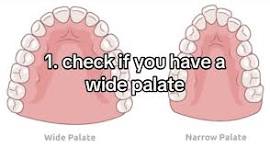

For a long time I have had issues with breathing through my nose and have heard that a palate expander can actually help with that, I feel like my tongue also doesn’t have enough space to properly mew

For a long time I have had issues with breathing through my nose and have heard that a palate expander can actually help with that, I feel like my tongue also doesn’t have enough space to properly mew